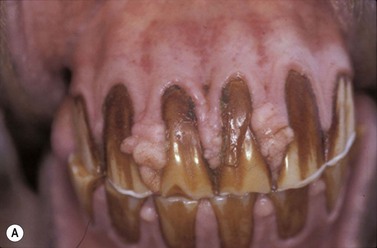

Squamous cell carcinoma (SCC) is probably the commonest oral neoplasm. Although mucocutaneous junctions are commonly affected with SCC outside the mouth, where there is an apparent correlation with non-pigmented skin and possibly with high levels of ultraviolet light, many of the most severe and aggressive SSC tumors occur within the mouth.46 The role of ultraviolet light in the pathogenesis of facial and lip carcinoma is uncertain, but the Clydesdale breed and horses with non-pigmented skin of the face and lips are more often affected than other breeds and colors. Putative carcinogens include chronic irritation, such as epulis, foreign body reactions, chronic wounds, and possibly dietary factors. Older horses are more likely to be affected.

There is often a suggestion that the primary tumor develops in the paranasal sinuses or nasal cavity and the destructive tissue involves the hard palate, but it may be difficult to identify whether the primary lesion is in the sinus or the hard palate.47 SCC possibly arises in chronically irritated hyperplastic alveolar epithelium in cases of chronic periodontitis.

Clinical features

SSC tumors are characteristically slow growing but occasionally have a more rapid course. They can be proliferative at least initially, but usually become very destructive, ulcerative and infiltrate widely into local tissues of the mouth including the lips, buccal mucosa, hard palate and tongue.48 Early lesions may simply resemble a non-healing wound but more advanced, destructive carcinoma lesions have a characteristic foul odour.

Metastases to local lymph nodes can occur, although the general sentiment is that they do not do so commonly.49 In theory, they may disseminate to the lungs and elsewhere. However, this behavior is rare in oral forms of SCC.50

Oral SCC may involve the lips (Fig.11.13A), hard palate51 (Figs 11.13B,C), tongue51,52 (Figs 11.13D,E) or oral mucosa (Fig. 11.13F). It is also quite common for oral SCC to invade the nasal cavity and the paranasal sinuses (often to the point of gross distortion or obstruction to airflow).53 Some SCCs involve the base of the tongue (Fig. 11.13E) and pharynx (Fig. 11.13G) and can physically affect their function. Where the nasal cavity and paranasal sinuses are involved, there may be altered airflow (or even complete obstruction of the ipsilateral nostril). Horses with pharyngeal and lingual SCCs may present with dysphagia of progressive, insidious onset. In all cases, weight loss and poor general health are common.

The location of SCC means that tumors are frequently detected late when a large invasive mass may already be present projecting from the gum or hard palate as a grayish, ulcerated and bleeding mass. Where the tumor surrounds a tooth, this may become dislodged, and in almost all cases there is a fetid odor from the mouth. Involvement of the lips and gums is usually clinically obvious; early tumors are often identified incidentally during routine dental procedures.